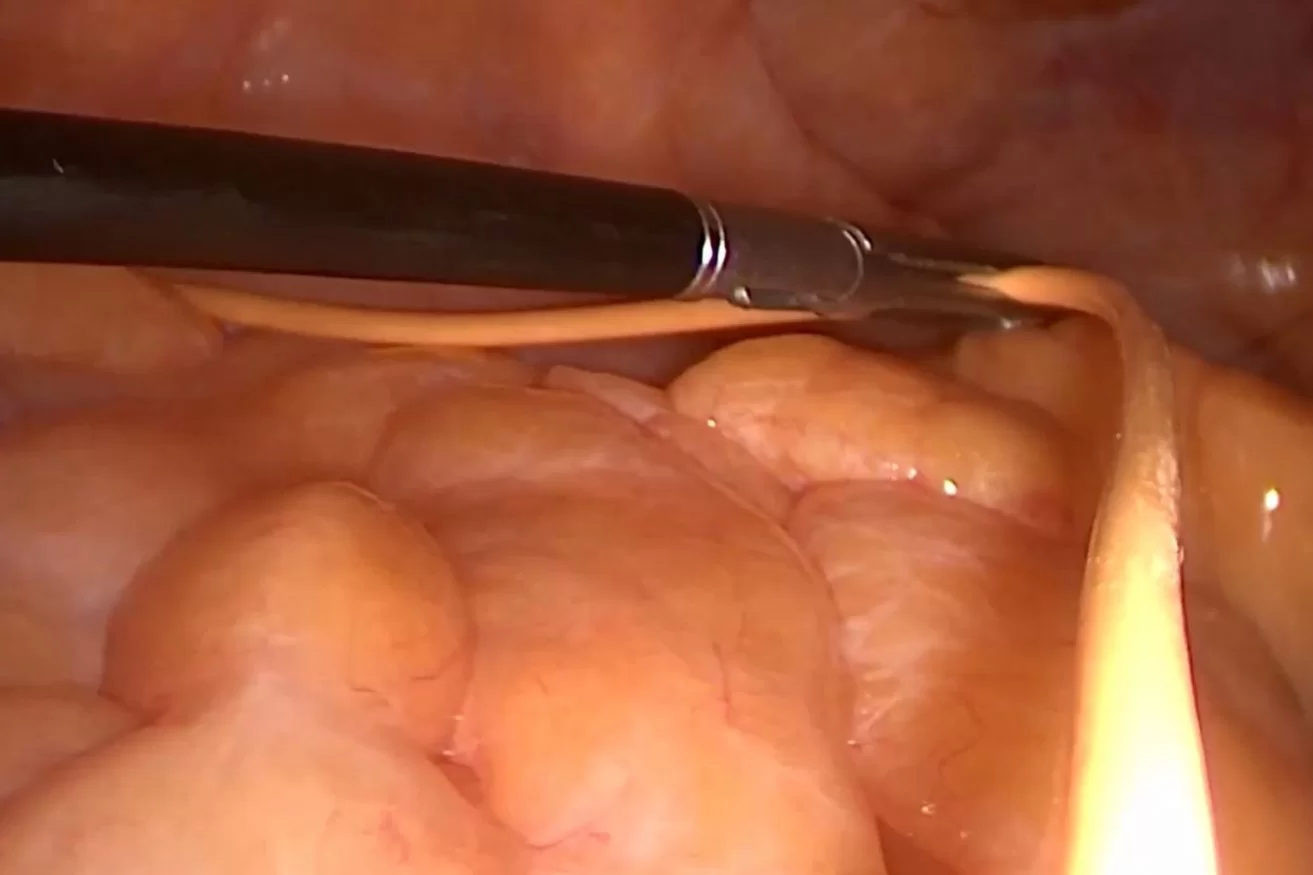

Υδροκέφαλος Φυσιολογικής Πίεσης – Λαπαροσκοπική τοποθέτηση περιφερικού καθετήρα

Ασθενής άνδρας 82 ετών με ιστορικό υδροκέφαλου φυσιολογικής πίεσης (Normal Pressure Hydrocephalus – NPH) στον οποίο είχε τοποθετηθεί κοιλιοπλευριτική (κοιλιοϋπεζωκοτική) παροχέτευση, λόγω αδυναμίας τοποθέτησης του